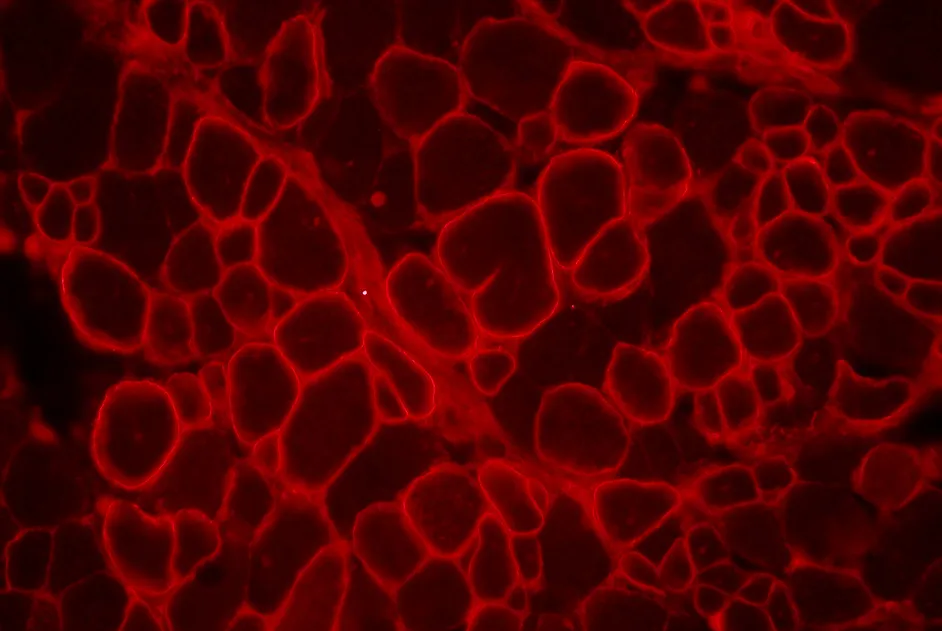

Sarepta Therapeutics, dans un communiqué de presse daté du 1er octobre 2015, communique des résultats additionnels concernant l’évaluation de l’eteplirsen (oligonucléotide antisens visant le saut de l’exon 51 du gène DMD) dans la dystrophie musculaire de Duchenne.